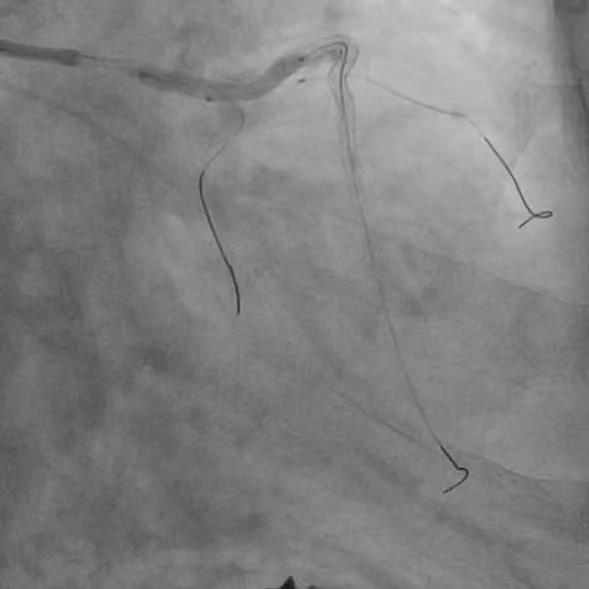

患者74岁,10年前因胸痛诊断为冠心病,在外院放过支架,但当时医生即明确告知家属,血管最严重的“总开关”左主干的地方钙化分叉,处理起来太危险,只是把难度相对不高的血管放了支架。近年来患者间断胸闷、胸痛,伴有心衰下肢肿胀,辗转来我院。冠脉CT显示冠脉严重钙化,因此安排冠脉造影检查。 ![]() ![]() 术前CTA提示左右冠支架术后且左主干重度钙化 (主干没有支架) 冠脉造影

![]() ![]() ![]() 左右冠脉造影:右冠脉支架远段已完全闭塞,旋支远端完全闭塞,前降支中远段重度狭窄,左主干重度钙化分叉。 手术策略